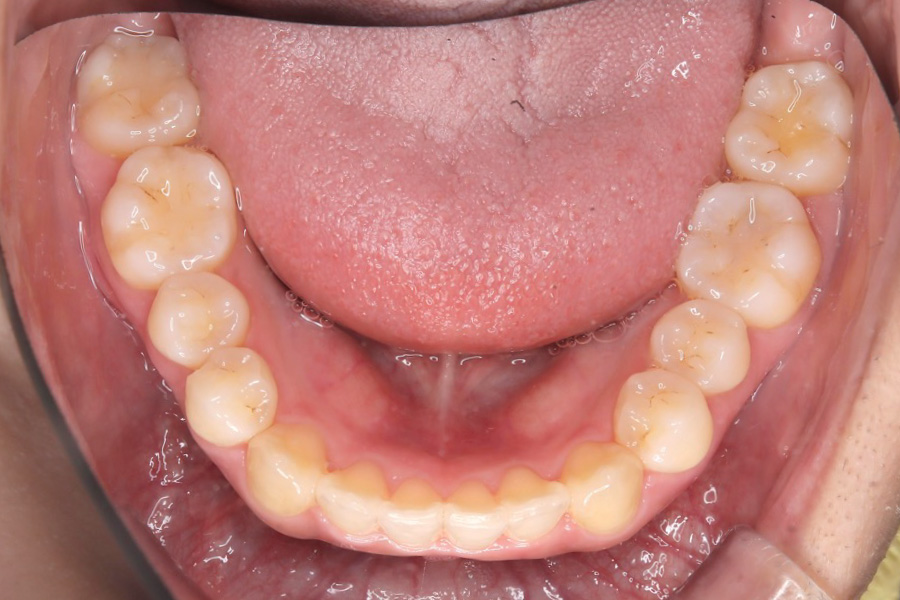

【20代女性】

全体のガタつきを

インビザライン矯正で治療したケース

治療後

主訴 全体のガタつきが気になる

治療内容 インビザライン矯正

非抜歯